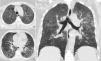

We report the case of a 69-year-old woman who presented to our department in April 2020, during COVID-19 pandemic. On admission, the patient described a 10 day history of progressive dyspnoea and chest pain. There was a 11% of weight loss and occasional wrist and ankle arthralgia, without myalgia, fever or cough. Relevant clinical history included hypertension, allergic rhinosinusitis and psoriasis (on cyclosporine treatment, discontinued in 2018). On physical exam she had tachypnoea, inspiratory crackles in the lung bases and a peripheral oxygen saturation (SpO2) of 89%. Laboratory findings revealed normal white blood cell count, an increased high-sensitivity C-reactive protein (3.70mg/dL N.R.<0.5mg/dL), lactate dehydrogenase (308U/L >250U/L) and erythrocyte sedimentation rate (60mm/h <20mm/h) with procalcitonin value within the reference range (0.09ng/mL <0.5ng/mL). Immunological and microbiological studies (including a swab test for RT-PCR SARS-CoV-2) were negative. Chest radiography showed diffuse bilateral symmetric ill-defined air-space opacities. Chest CT displayed diffuse bilateral ground-glass opacities with lobular spared areas (mosaic attenuation pattern), ill-defined centrilobular ground-glass nodules and mild interlobular thickening, however without the characteristic distribution of COVID-19 (Fig. 1).